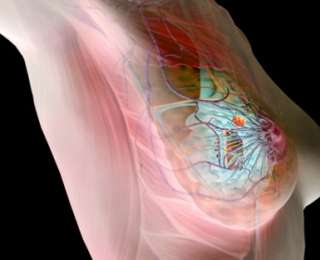

Знаете ли вы, что в России от рака молочной железы ежегодно погибает 25 тысяч женщин? Согласно подсчетам, риск заболеть страшным недугом имеется у каждой восьмой россиянки. Предотвратить беду может своевременная диагностика.

Проблема онкологических заболеваний стала за последние годы особенно острой не только в России, но и во всем мире. К неутешительному выводу пришла Всемирная организация здравоохранения (ВОЗ): рак молочной железы на данный момент является одним из наиболее распространенных онкологических заболеваний в мире, от которого умирают женщины. Динамикой роста заболеваемости обеспокоены и российские врачи:

Первые тревожные признаки, на которые важно обратить внимание – узелки, припухлости и уплотнения. Обнаружить их женщина может сама при пальпации груди. Основными симптомами являются:

- Узел или уплотнение, которое долгое время не проходит.

- Изменения поверхности кожи или формы соска и груди.

- Непривычные дискомфортные или болевые ощущения.

Как правило, к концу менструального цикла симптомы сами собой исчезают. Диффузно-фиброзные изменения тканей характерны и для доброкачественного воспалительного процесса. Но это не повод расслабляться. Рак молочной железы может протекать и в скрытой форме! Признаки заболевания просто нельзя будет увидеть или прощупать. Если вы столкнетесь с одним из вышеуказанных симптомов – не поленитесь обратиться к специалисту. Ведь ранняя диагностика по праву считается самым лучшим средством защиты от смертельно опасного недуга.